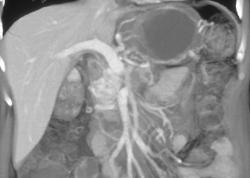

Collateral Vessels Due to Splenic Vein Occlusion